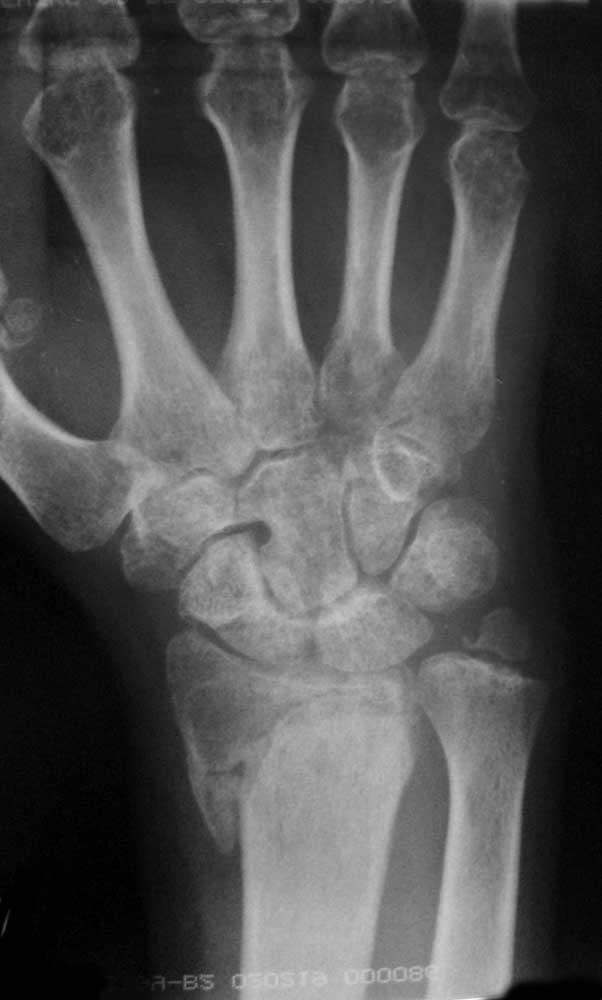

Re: Перелом дистального луча

То же самое, только в профиль

правая кисть - прямая проекция и разные степени проекции

прямая проекция и с согнутыми в кулак пальцами

боковая и косая полупронированная проекции